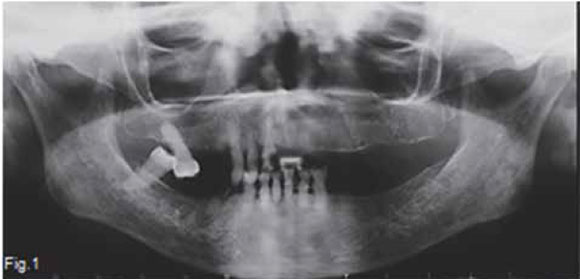

Below are images of a condition caused by a deficiency of organic bone matrix; however, there is normal mineralization of the remaining bone. This condition is a common disorder affecting post-menopausal middle-aged women .What are the important radiological findings and diagnosis?

A figure 1 and 2 are pantomograhs of two elderly woman shows thinning of the cortex at the inferior border at the angle of the mandible. There are cortical laminations with endosteal detachment. The alveolar bone is denser (darker) than normal, although the teeth are exposed correctly; trabeculae are fewer in number, coarser and showing reduced density. Figure 3 of another patient shows a classic appearance of the same condition in the vertebral column; loss of horizontal trabeculae; thicker, more prominent vertical trabeculae; and more radiolucent vertebral body (red arrow). The posterior vertebral plate is coarser, with irregular endosteal surface. There is a wedge-shaped deformity of the disk, as can be seen by the V-shape of the intervertebral space (green arrow). In several places there is complete loss of the intervertebral space. A diagnosis of osteoporosis was made in all these cases. Figure 4 demonstrates changes from normal bone (a) to severe osteoporosis (b). Primary osteoporosis refers to a condition that is not associated with any of the diseases known to cause an osteoporotic state. No known causal condition has been established. According to Garn (1970), normal bone mass increases as a person progresses from infancy to 30 to 40 years of age and then decreases continuously at a rate of 8% per decade in women and 3% in men. This bone loss is particularly evident in the cortex and continuous until a person dies. Fifty percent of men exhibit cortical bone erosion by age 80; among women, 50% show cortical bone loss by the age of 70 and 100% by age 90. Trabecular bone is affected earlier than cortical bone, and the vertebral column is the prime site of advanced cases. In women osteoporosis results from increased resorption that is associated with menopause. During menopause, there is diminished production of oestrogens, which tend to protect the skeleton against the resorbing action of parathyroid hormone. In men primary osteoporosis may develop from diminished androgen production. It has been shown in aging men that parathyroid levels increase, yet urinary excretion of calcium decreased with age. It is presumed that there is an increased tubular resorption of ionic calcium resulting from mild secondary hyperparathyroidism.This calcium-saving mechanism is missing in women. Regardless of the cause, osteoporosis results in an increase of fractures in the axial skeleton and possibly tooth loss and alveolar ridge resorption in the jaws.